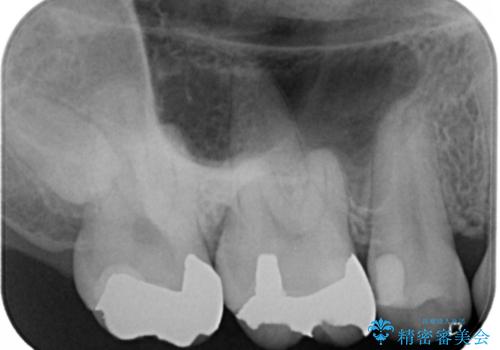

- 右上6番の銀歯のやりかえを希望し来院された患者様です。

切削量や形状からインレーでの治療を計画しました。

ご本人が金歯を希望されたため、ゴールドインレーでの治療を選択しました。